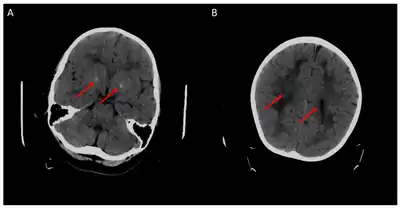

- Mafi S, Laroche-Raynaud C, Chazelas P, Lia AS, Derouault P, Sturtz F, Baaj Y, Froget R, Rio M, Benoist JF, Poumeaud F, Favreau F, Faye PA (October 2020). "Pharmacoresistant Epilepsy in Childhood: Think of the Cerebral Folate Deficiency, a Treatable Disease". Brain Sciences. 10 (11): 762. doi:10.3390/brainsci10110762. PMC 7690394. PMID 33105619.